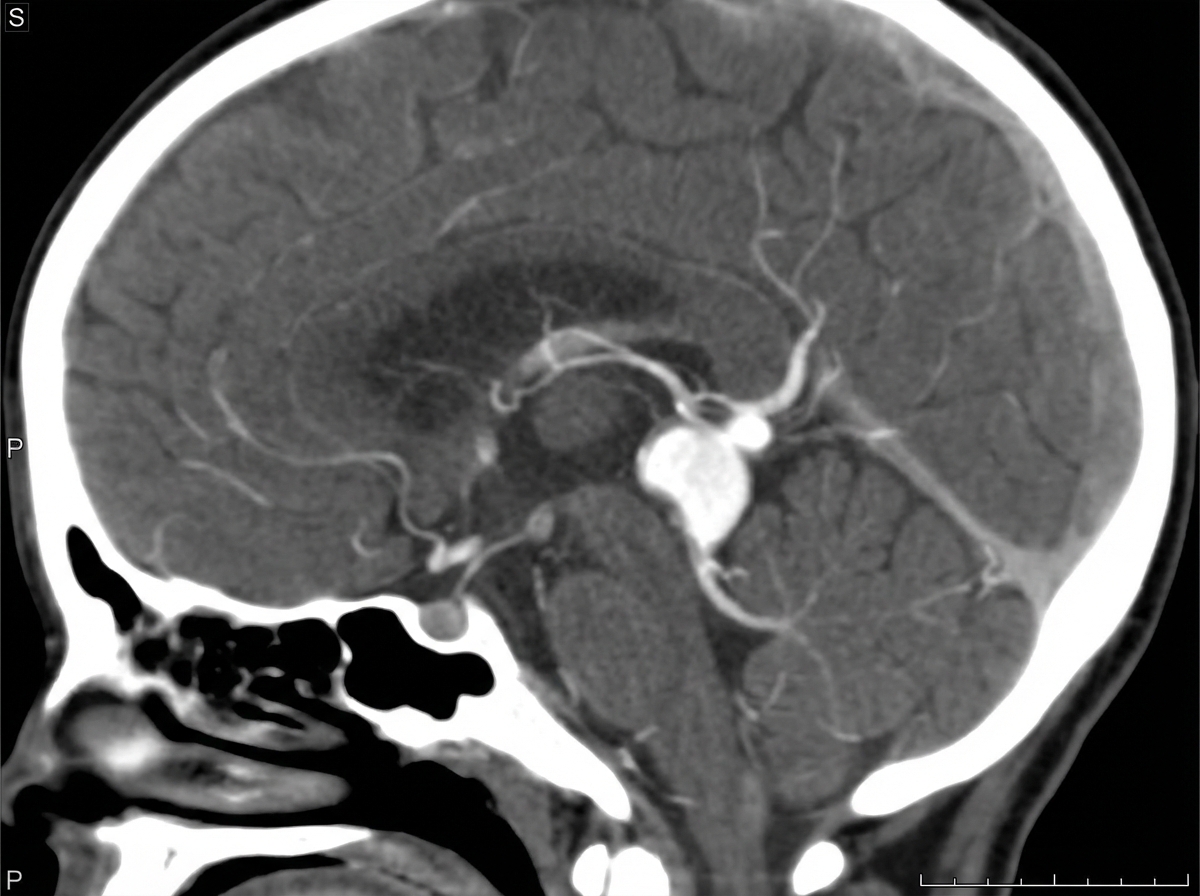

A neonate presents with a left-to-right shunt and high cardiac output heart failure. CT angiography of the neonate is shown. What is the diagnosis?

Explanation: ***Vein of Galen malformation*** - Causes **left-to-right arteriovenous shunting** that directly leads to **high-output cardiac failure** in neonates due to the large volume of blood bypassing normal capillary resistance. - CT angiography typically shows a **dilated midline venous structure** in the posterior third ventricle region with prominent **feeding arteries** and **venous drainage**. *Sagittal venous thrombosis* - Would present with **venous stasis** and **increased intracranial pressure**, not left-to-right shunting or cardiac failure. - CT angiography shows **absent flow** in the superior sagittal sinus with possible **venous infarcts**, not arteriovenous connections. *Intracranial hemorrhage* - Presents with **mass effect** and **neurological deterioration**, not cardiac symptoms or shunting. - CT shows **hyperdense blood products** in brain parenchyma, ventricles, or subarachnoid space, not vascular malformations. *Arnold-Chiari malformation* - A **structural brain malformation** involving **cerebellar tonsillar herniation** through the foramen magnum. - Does not cause **cardiac failure** or **arteriovenous shunting**, and appears as **posterior fossa crowding** on imaging.